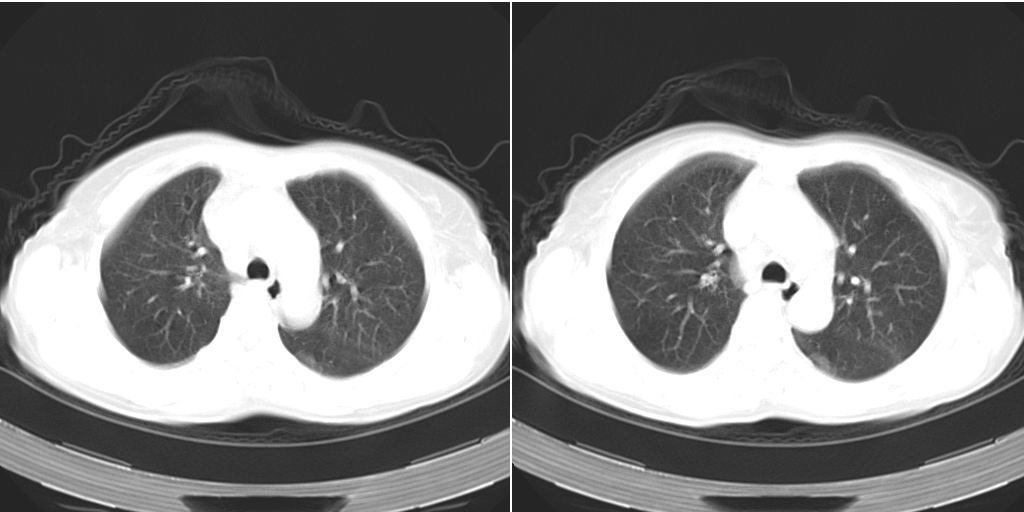

以下是引用dyqct在2007-1-23 15:01:00的发言:[br]左肺下叶实变、略萎陷,近肺门下部密度不均。上腔静脉后及隆突前见肿大淋巴结。余未见异常。[br]考虑:1、左肺下叶中心型肺癌伴肺不张、纵隔淋巴结转移;[br] 2、建议增强扫描并做任意平面重建确定肿块范围及支气管受累情况。

以下是引用同在2007-1-23 19:59:00的发言:[br]左肺下叶中央型肺癌伴肺不张及纵隔淋巴结转移.